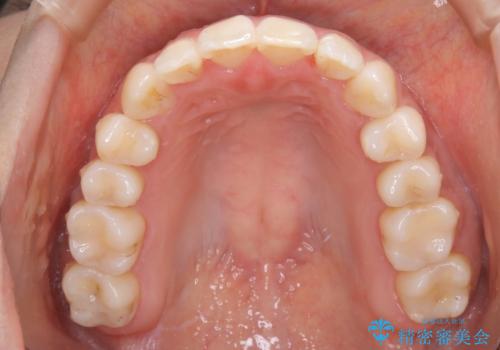

【非抜歯】インビザライン 隠れた前歯を並べる矯正治療

遠心移動

非抜歯で矯正を行う場合にガタつきの改善に必要なスペースを作るために歯の遠心移動を行います。

最初の位置から奥に歯を移動させていくことで前歯のガタつきを改善したり、前歯の位置を後方に移動させることが可能となります。